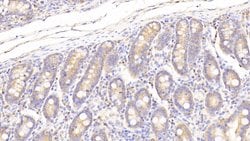

PON2 Polyclonal Antibody for Western Blot, IHC (P)

This gene encodes a member of the paraoxonase gene family, which includes three known members located adjacent to each other on the long arm of chromosome 7. The encoded protein is ubiquitously expressed in human tissues, membrane-bound, and may act as a cellular antioxidant, protecting cells from oxidative stress. Hydrolytic activity against acylhomoserine lactones, important bacterial quorum-sensing mediators, suggests the encoded protein may also play a role in defense responses to pathogenic bacteria. Mutations in this gene may be associated with vascular disease and a number of quantitative phenotypes related to diabetes. Alternatively spliced transcript variants encoding different isoforms have been described.Specifications

| Immunohistochemistry (Paraffin), Western Blot | |